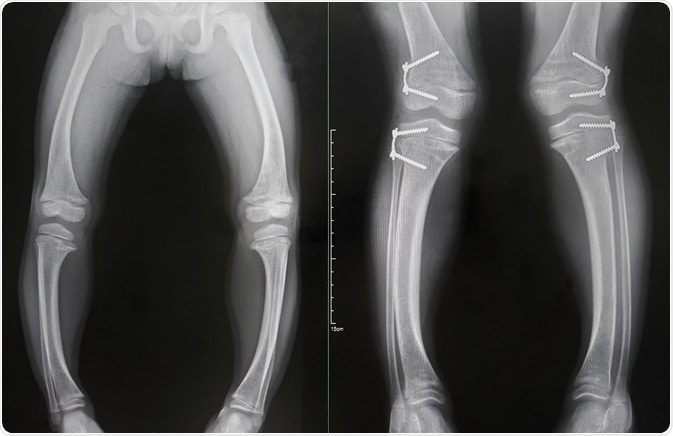

ricketsRickets. Image Credit: Bunsinth-Nan-Pua / Shutterstock.com